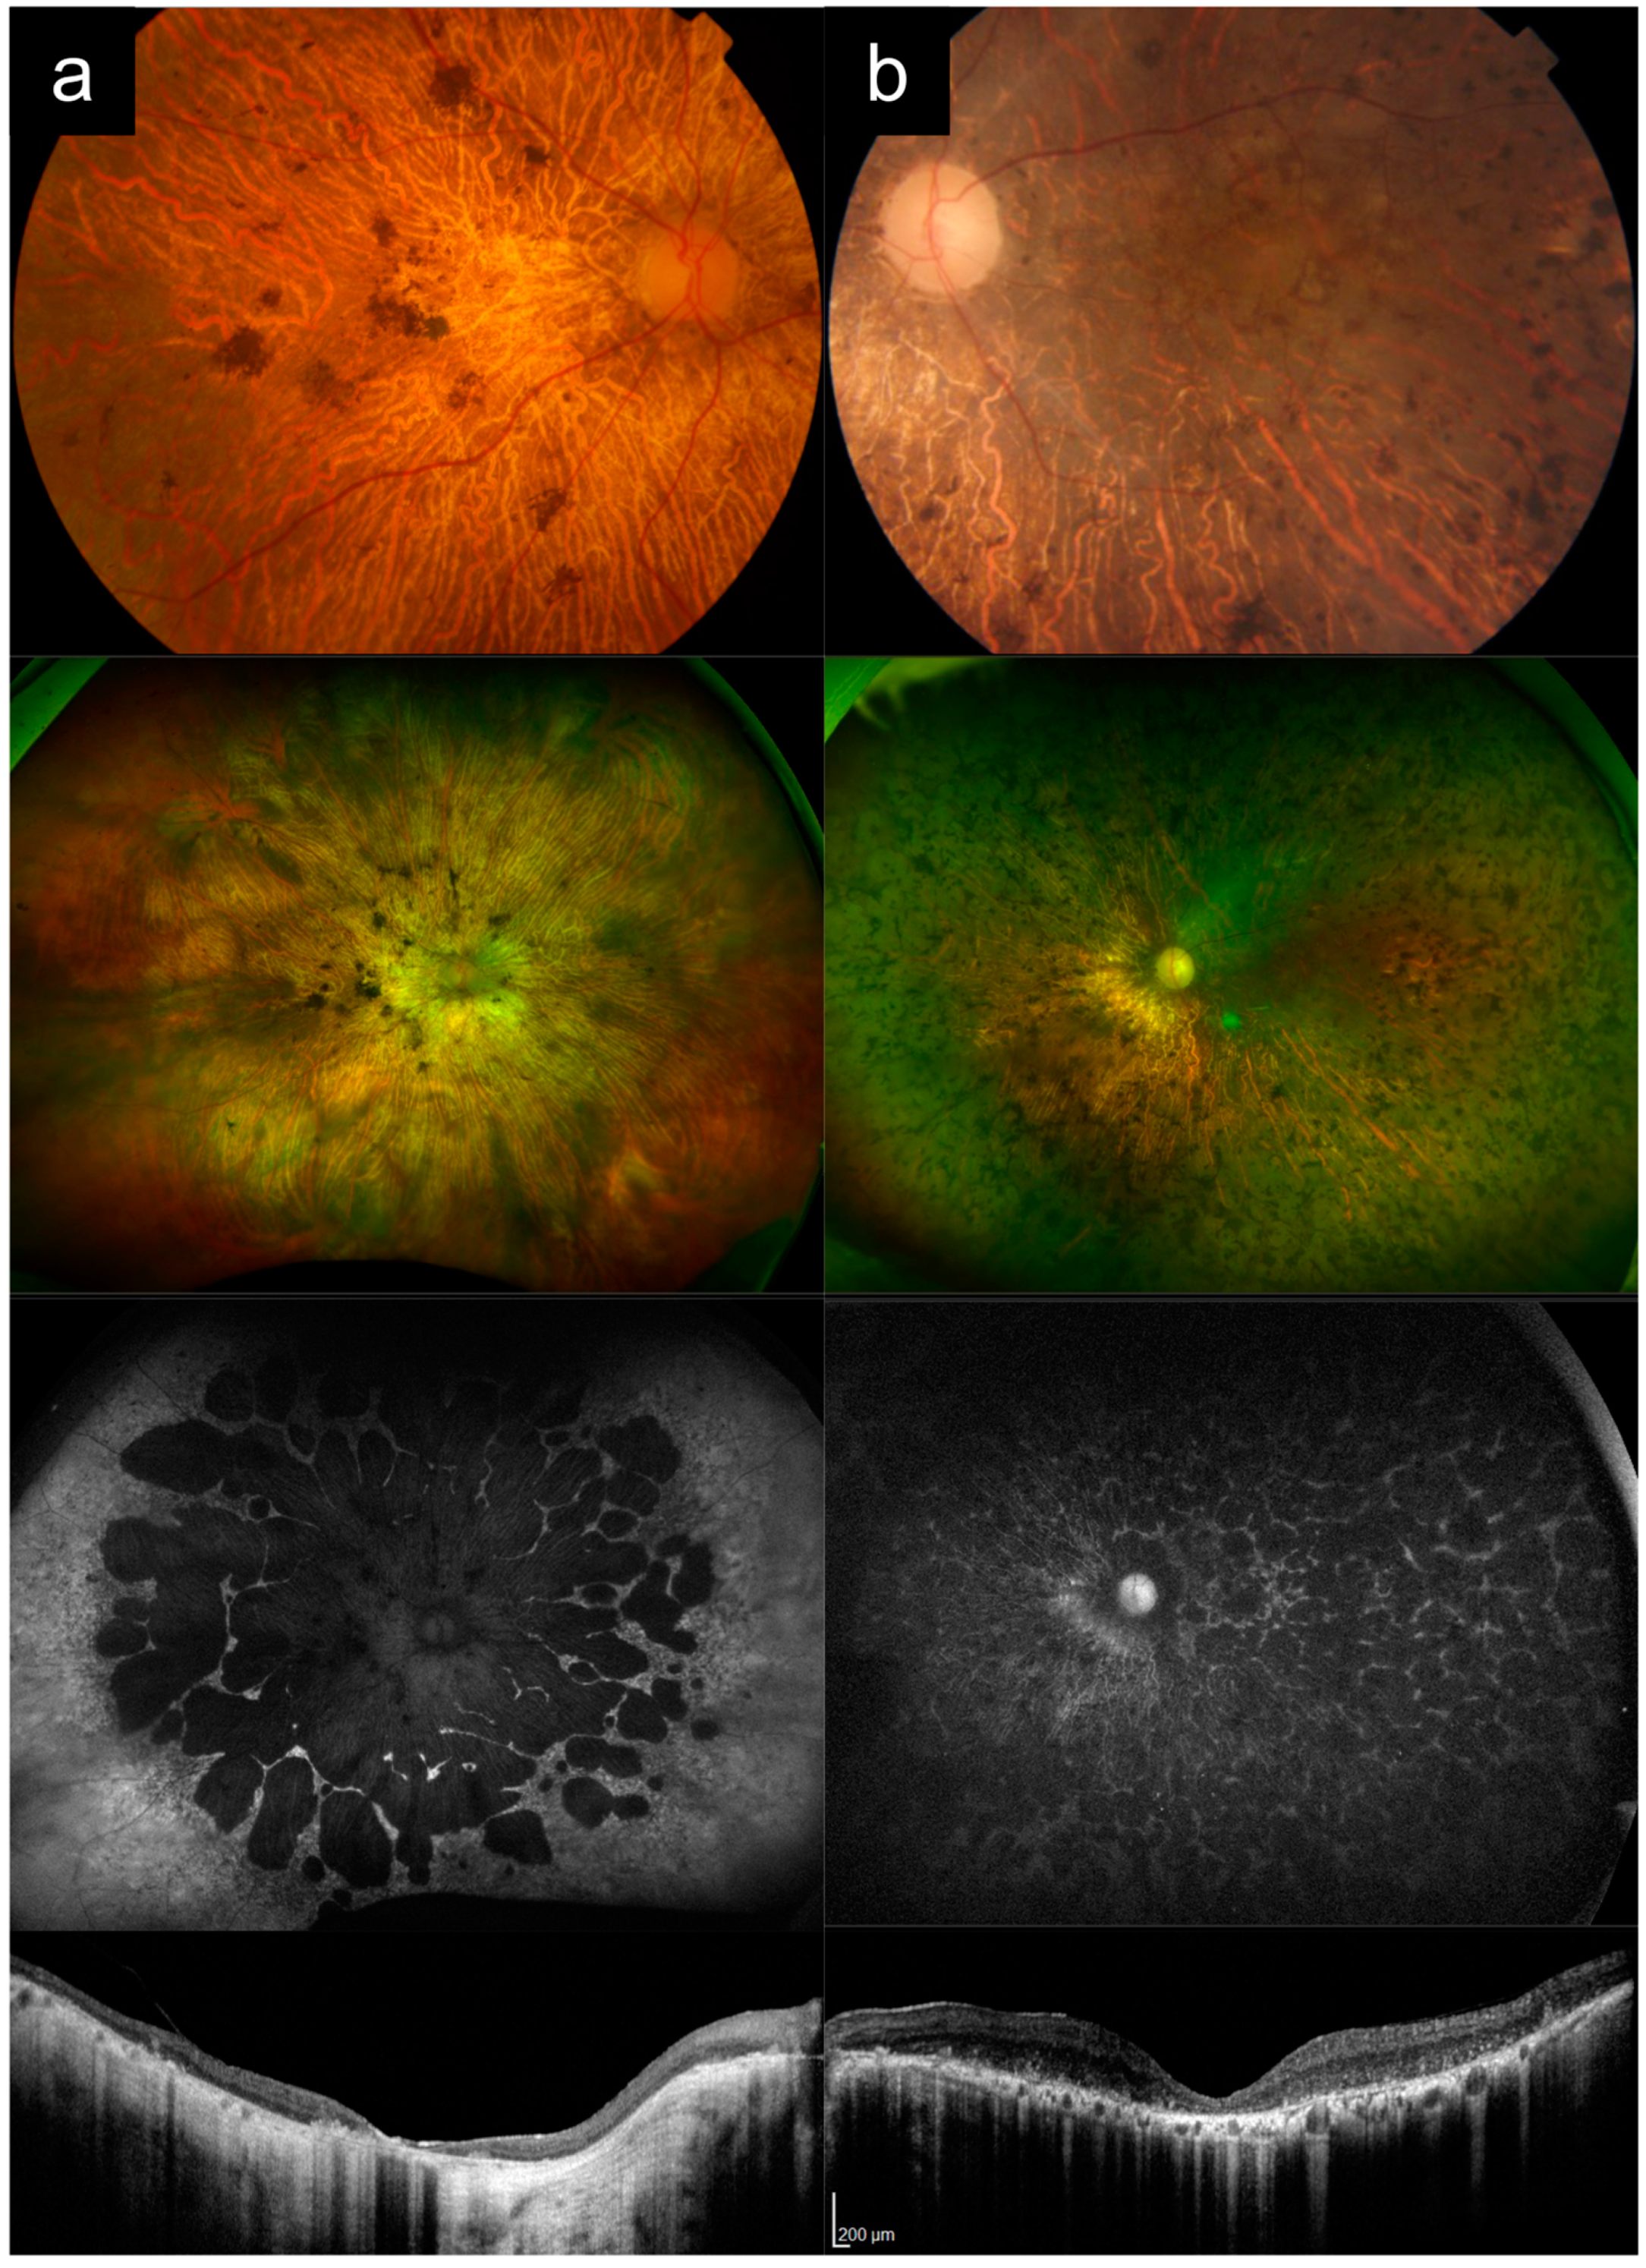

3.6. Cases 6a versus 6b: Severe, Early-Onset ABCA4-RD versus Leber Congenital Amaurosis

Case 6a presented with bilateral poor vision from 5 or 6 years old. At 7 years old, BCVA was 6/45 and 6/18 in the right and left eyes, respectively. She had no nystagmus. Vision progressively worsened over time.

Figure 6a shows imaging of her right eye from her late teens. VA was HM in both eyes at this time. CFP and UWF imaging show diffuse widespread granular RPE atrophy with a yellow appearance to the fundus, scattered pigment clumps and significant arteriolar attenuation. UWF AF imaging shows that the atrophy is more central and centrifugal in distribution, with clear peripapillary sparing. OCT imaging showed diffuse outer retina and RPE atrophy, with mild diffuse thickening of the inner retinal layers, and mild loss of inner retinal lamination temporally. Genetic testing revealed two causative

ABCA4 variants in this patient (

Table 1).

Case 6b presented with nystagmus, a divergent squint and poor vision noted in the first 3 months of life. At 1 year old, VA was about 6/120 and 6/200 in the right and left eyes, respectively.

Figure 6b shows imaging of the right eye from 7 to 14 years of age. Visual acuity in the right eye was light perception (LP) at that time. CFP and UWF imaging show diffuse widespread granular RPE atrophy with a yellow appearance to the fundus and scattered pigment clumps. OCT imaging showed diffuse outer retinal and RPE atrophy, along with diffuse thickening and loss of distinct inner retinal lamination. Genetic testing disclosed a pathogenic and likely pathogenic

CRB1 allele, c.3153G>A p.W1051X and c.3493T>C p.C1165R.

Case 6a illustrates that a severe, early-onset

ABCA4-RD can occasionally mimic Leber congenital amaurosis (LCA), and in this case particularly with LCA caused by

CRB1 variants. The

ABCA4-RD case demonstrated widespread diffuse granular RPE atrophy, pigment clumps, and some mild inner retinal thickening and loss of lamination, which are more typically hallmarks of

CRB1-associated disease. In this case, the key distinguishing features are the age of onset of visual loss, nystagmus, and the distribution of disease (

Table 2). The onset later in life around 5 or 6 years of age, the absence of nystagmus, and the centrifugal distribution and peripapillary sparing (evident on UWF AF imaging) point towards

ABCA4-RD rather than LCA. Some other potential features that are more consistent with

CRB1-associated LCA are the relative lack of arteriolar attenuation (in relation to the severity of disease), and the more significant loss of retinal lamination on OCT. Other features which tend to occur in

CRB1-associated disease (which are absent in this case) are periarteriolar preservation of the RPE, schitic change in the retina, and secondary Coat’s-like vascular exudation.